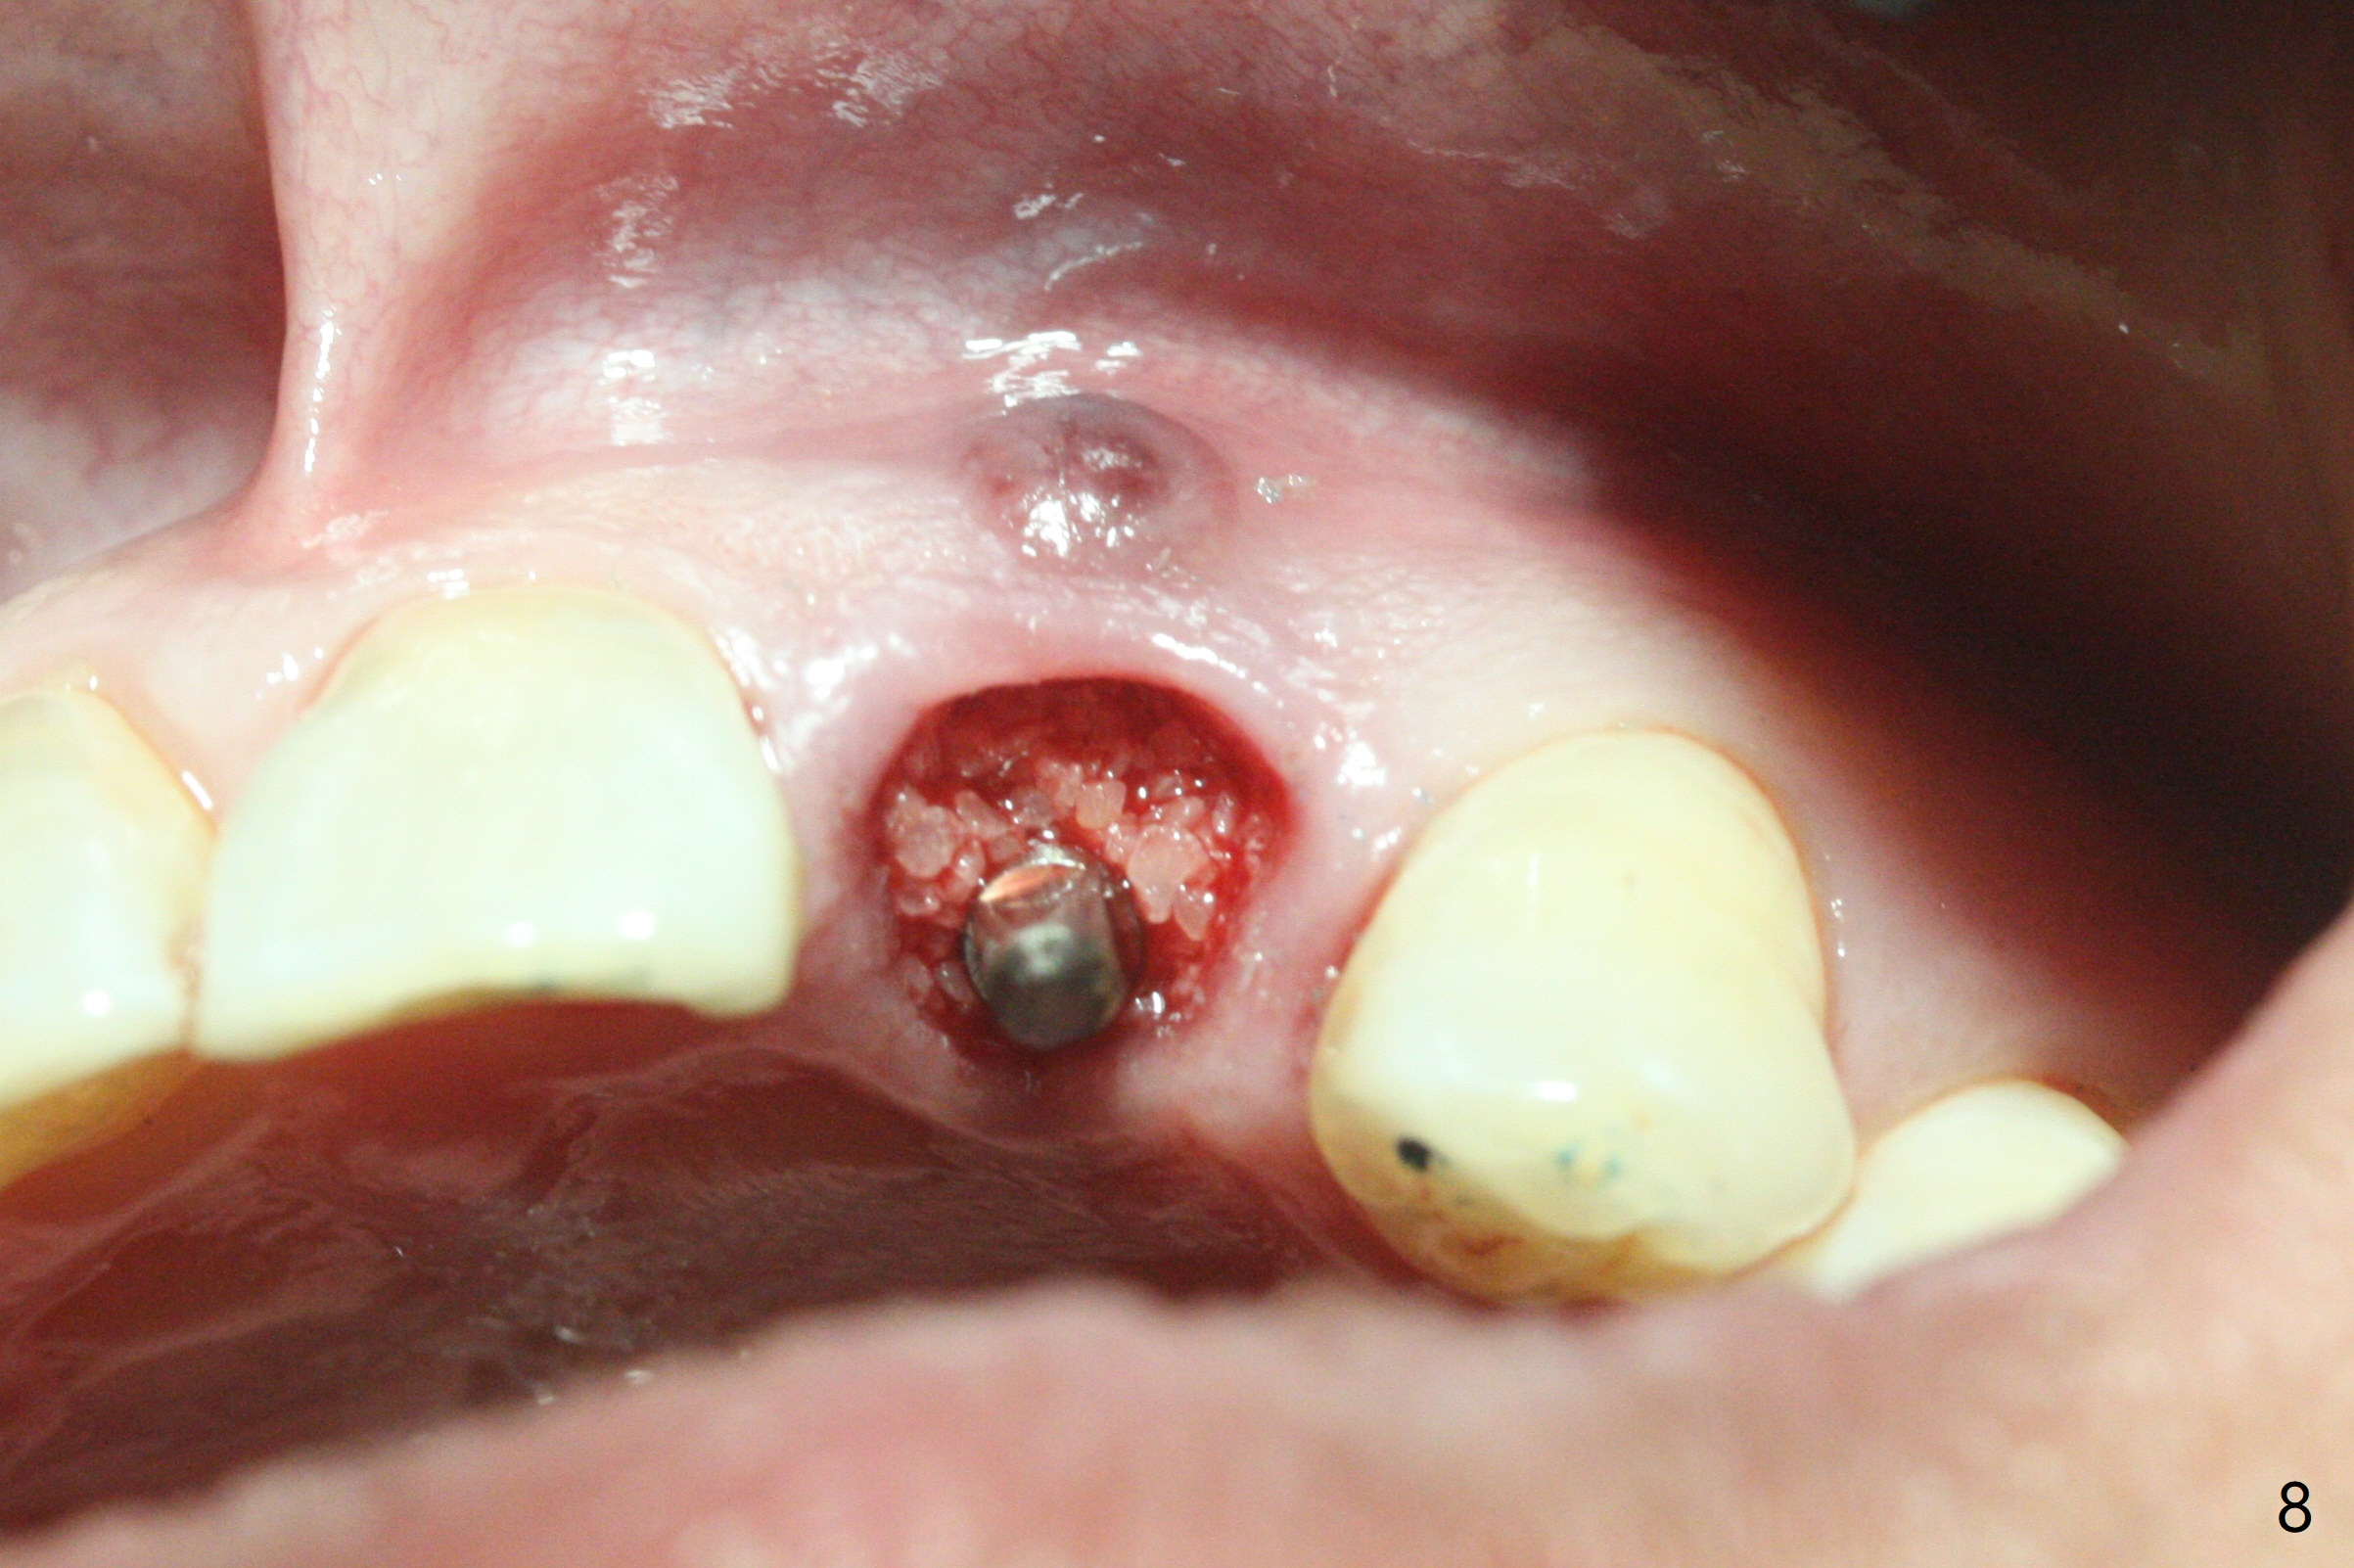

病人回来带来瘘道(图一),不过不会增加难度,病牙去除,它便自动消失。尽管颊侧骨壁完全失去,颊侧牙龈仍丰满(图二),为什么呢?第一,因为粗大牙根存在,第二两旁牙齿,牙槽骨撑着帐篷(侧切牙颊侧牙龈),第三,牙冠。为了防止术后牙龈塌陷,尽量不切开,即刻放置植体(牙根);由于前牙缘故,这次植体不能很大,所以植骨必须过度(over grafting),最后即刻制作临时牙冠,撑住牙龈。这就是所谓每个人进入角色。这个牙根有一种先天性畸形:dens in dent (图三(腭侧观):箭头)。尽管腭侧牙根畸形,腭侧骨壁吸收临床上并不严重,所以钻洞仍偏腭侧。当预定最后钻头还在钻洞时,填入大量粘性骨块(图四:*),细长植体还没有完全卡入鼻底(图五),最后好像可以(图六,七)。植体,骨粉入位(图八),最后临时牙冠出场(图九)。尽管植体小,术后一周临时牙冠仍然可以维持牙龈原有形状(emergency profile,图十:箭头(*:树脂强化牙冠固定))。图十一以不同角度显示瘘道缩小。术后三周取出有些松动的临时牙冠,骨粉虽然还没有被肉芽组织整合,但是显得正常,周围牙龈健康(图十二)。术后4个月牙龈形态正常(图十三),没有触痛;颊侧骨板轻度凹陷(图十四);骨粉仍在原位(图十五)。术后7个月骨粉仍在原位(图十五,十六,但是冠部密度减低(可能骨粉流失,需要牙周或者树脂敷料保护)),没有螺纹暴露。但是牙冠边缘暴露,说明牙龈收缩(图十七,与图十三对比),颊侧骨板仍塌陷(图十八)。插入龈线取得多个目的:修整基台边缘,取模,颊侧牙龈推向颊侧,有利于即将衬里牙冠龈缘进入龈下(图十九)。取模后牙冠边缘(图二十:<)衬里,然后修整,变窄,以便插入龈下,促进颊侧牙龈下降(图二十一,二十二)。术后8个月牙冠粘固前牙龈健康(图二十七,八),牙冠(图二十九)固位后,病人满意(图三十),咬合调整(图三十一),注意腭侧粘固粉流出通道(<)。